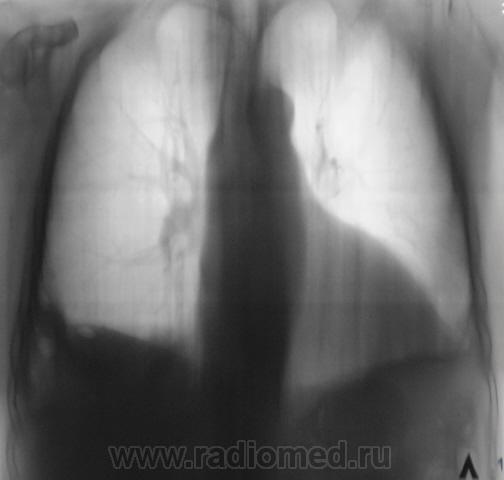

Травмы не было, и брюшной полости в том числе. Пациентка в течение 1 месяца "народными средствами" лечилась от "простуды". Но темперетура поползла и бабушка обратилась в больницу, участковым терапевтом была направлена на рентгенографию - 1 снимок.

После производства снимка (ургентном порядке), по-сему снимок в одной проекции, так как терапевт, аускультативно ничено не услышал, заказал только прямую проекцию, а лаборант и сделал одну проекцию.

Пациентку весьма интенсивно начали лечить в терапии, но стало хуже пациентке, начала "качать жидкость", справа, кроме всего прочего зарегистрировали пневмоторакс, был вызван их области торакальщик, который спунктировал около 3 литров справа, но с собой в область не взял, думал, по всей видимости, что "бабулька" загнется - вторая серия снимков.

Далее поключились хирурги, поставили дренаж и "бабушка" потихоньку стала выкарабкиваться - третья серия снимков, и даже начала ругаться, что чувствует себя уже хорошо, а мы тут её держим. Но её конечно "пользовали" еще, и в пятницу - последняя серия снимков - дали на контроль.